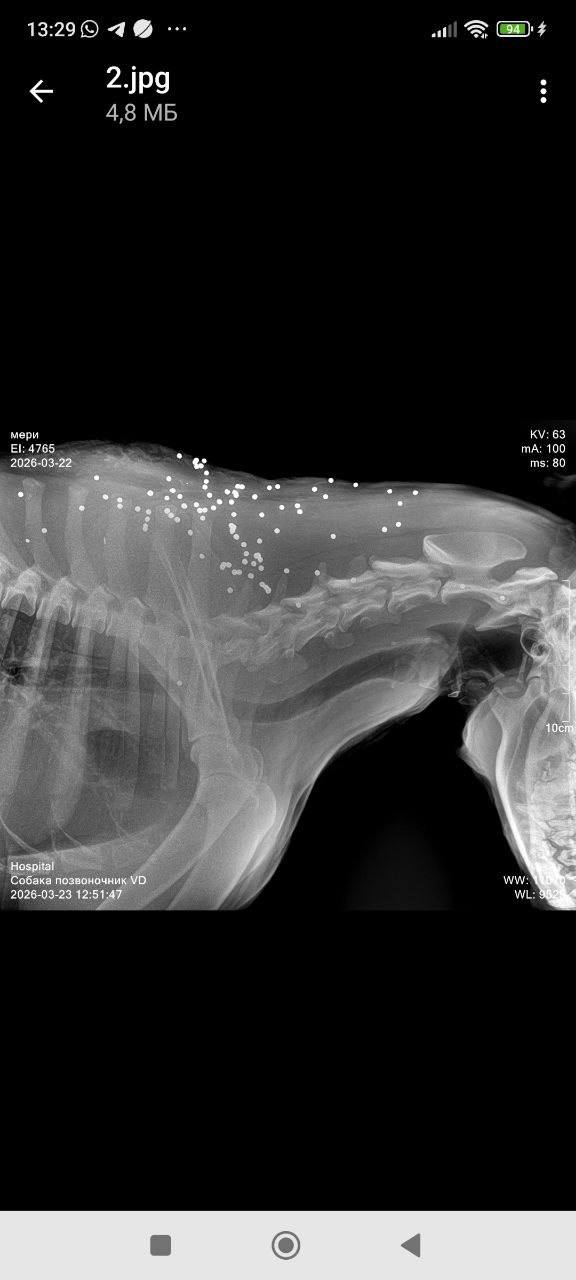

По словам очевидцев, пострадали как минимум четыре животных. Одна собака погибла на месте, две скрылись после ранений. Еще одно животное в тяжелом состоянии доставлено в ветеринарную клинику. Врачи борются за его жизнь.